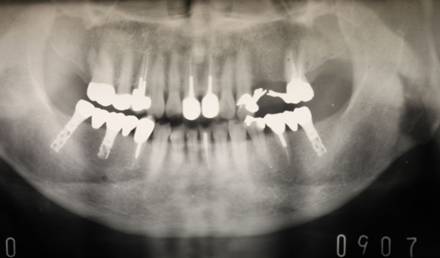

術前パノラマレントゲン写真。根の周りが黒くなり、骨がなくなっていることがわかります

治療後。歯周病で失われた骨が回復しています。使用インプラントはスプラインツイストです。